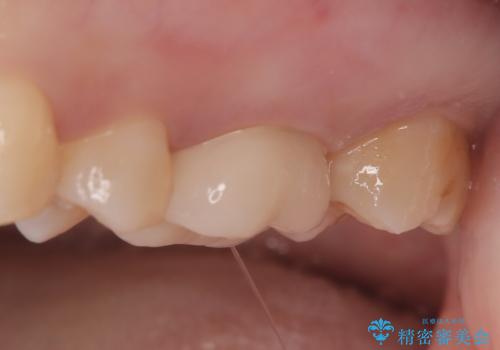

- メタルフリーを主訴に来院されました。

きれいな被せ物になり、患者さんにも満足していただけました。

歯牙の破折を防ぐために、セラミッククラウンにて修復しています。